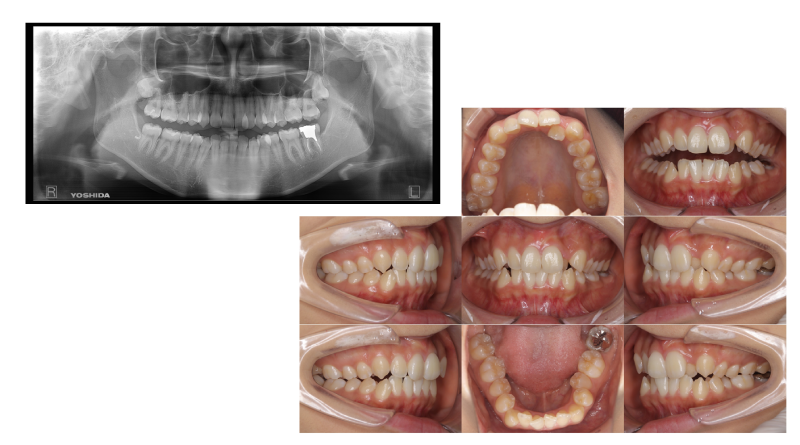

レントゲン撮影

虫歯や歯周病の進行具合を把握するためにレントゲン撮影をいたします。症状がまだ出ていない、目に見えない部分の虫歯や歯周病の検査も可能です。

虫歯や歯周病の進行具合を把握するためにレントゲン撮影をいたします。症状がまだ出ていない、目に見えない部分の虫歯や歯周病の検査も可能です。

口腔内の写真撮影

患者さんがご自身のお口の状態を分かりやすく確認していただくために、お口の中の写真を撮影いたします。治療の進行具合の確認にも利用できます。